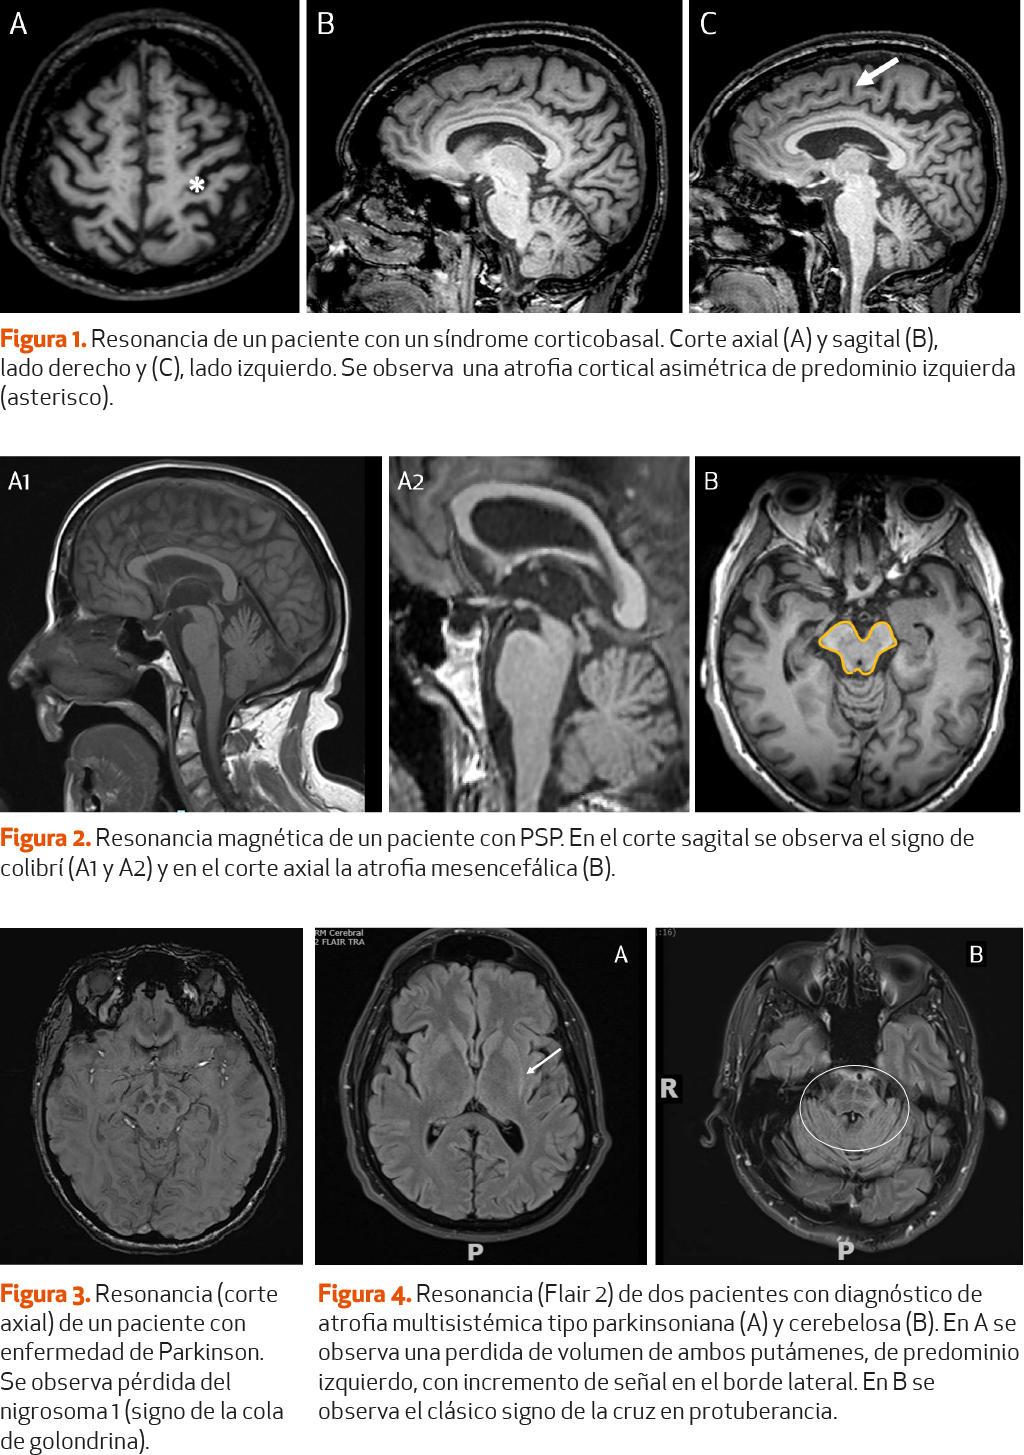

No sería preciso realizar un estudio de neuroimagen estructural (tomografía computarizada [TC] o RM craneal) de forma rutinaria a todo paciente con sospecha de EP78 (NE-III). Sin embargo, sí sería recomendable realizar una TC craneal a todo paciente con sospecha de patología cerebral (tumor, hidrocefalia, etc.) que pueda estar causando o agravando el síndrome parkinsoniano68 (NE-IV), así como una RM craneal en caso de sospecha de enfermedad vascular cerebral subcortical causante de un parkinsonismo vascular o datos atípicos que sugieren un parkinsonismo atípico68 (NE-IV). Para revisar en profundidad la utilidad de las técnicas de imagen en el diagnóstico y diagnóstico diferencial de la EP, remitimos al lector al capítulo 2, donde se trata este tema de manera específica (pag. 57).